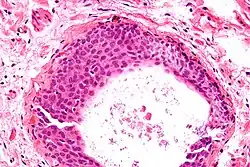

High magnification micrograph of a Brenner tumor showing the characteristic coffee bean nuclei which are also seen in Walthard cell rests. H&E stain.

- Uniform nuclei with irregular borders and nuclear grooves (insert image).

- Cyst (may also be solid nest) of transitional type epithelium.

- Eosinophilic luminal secretions.